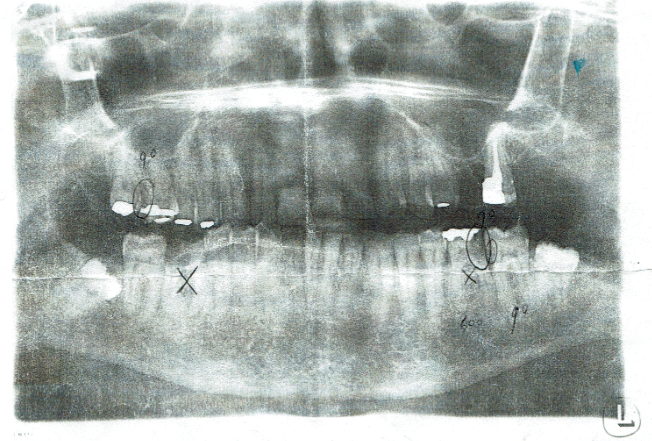

De begroting bovenstaand is gemaakt door tandarts Baeten op 24-02-2021 achteraf gezien klopt deze ook niet .Let op

- Op de foto lings boven van voor gezien 90 weet ik niet

- Kruisje rechtsboven hoevde niet verwijdert te worden daar had ik geen last van en staat ook niet op de begroting

- 600 Een wortelkanaal behandeling ??? .

- Naast element 37 waar 90 staat , de weledegeleerde tandarts Andre Padrao een wortelkanaalbehandeling in ziet ,was een vlekje . Dit kan ik nu nog bewijzen want er is niet geboord of niets. De weledelgeleerde tandarts Padrao kreeg de originele foto ter beschikking op 07-10-2021 hij zag hier er een wortel kanaal behandeling in

Foto 0 . 24-02-2021 is gemaakt door tandarts Baeten is niet geschikt om te oordelen of er twee wortelkanaal behandelingen nodig zijn

Ondanks alles heb ik toch veel aan de second opinions gehad . De begroting op 7-10-2021 is gebaseerd op foto 0 gemaakt op 24-02-2021 door tandarts Baeten . Deze foto is niet geschikt volgens de twee tandartsen boven zou er eerst een detail foto moeten worden gemaakt . volgens de e-mail van Juul op 20-01-2022 heeft de weledelgeleerde tandarts Padrao de begroting gemaakt op 07-10-2021.

| foto (24-02-2021) Hierop is de wortelkanaal behandeling van de weledelgeleerde tandarts Andre Padrao gebaseerd |

Hier had de weledelgeleerde tandarts Padrao volgens de twee secon opinons een detail foto moeten maken |

foto 1 (21-10-2021) foto2 (21-10-2021) foto3 (12-11-2021) foto 4 (12-11-2021)